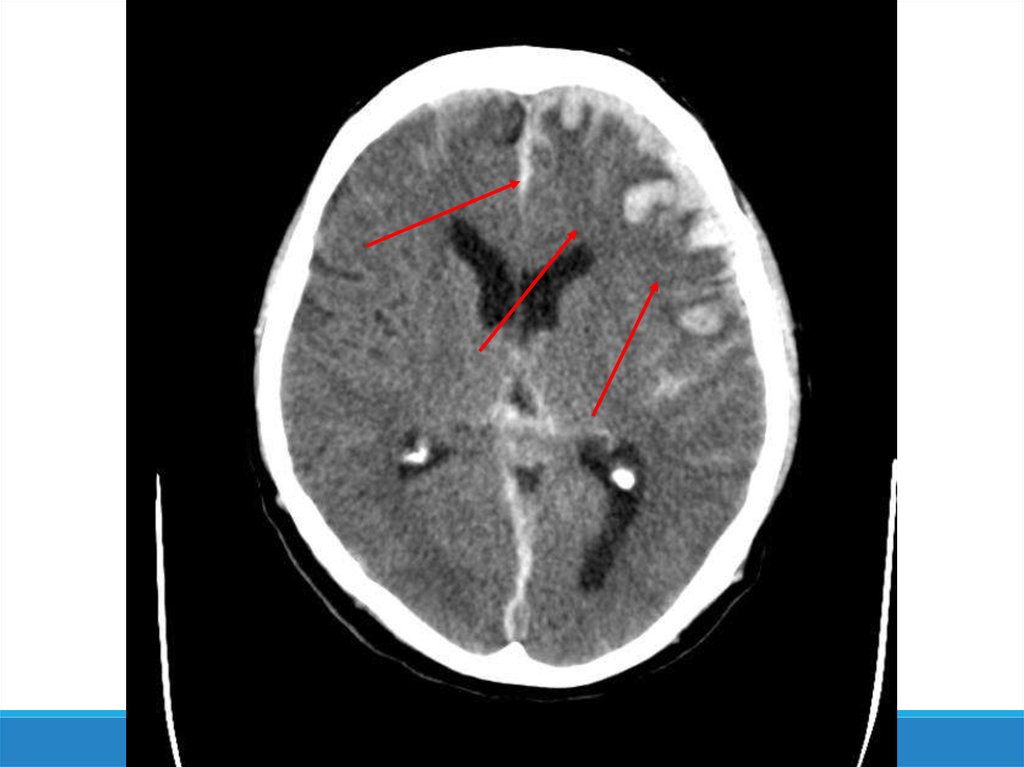

-Компьютерная томография

10. Патогенез ЧМТ

- Аксональные повреждения

- Цереброваскулярные нарушения

- Посттравматическая ишемия мозга

- Отёк мозга

- Внутричерепная гипертензия